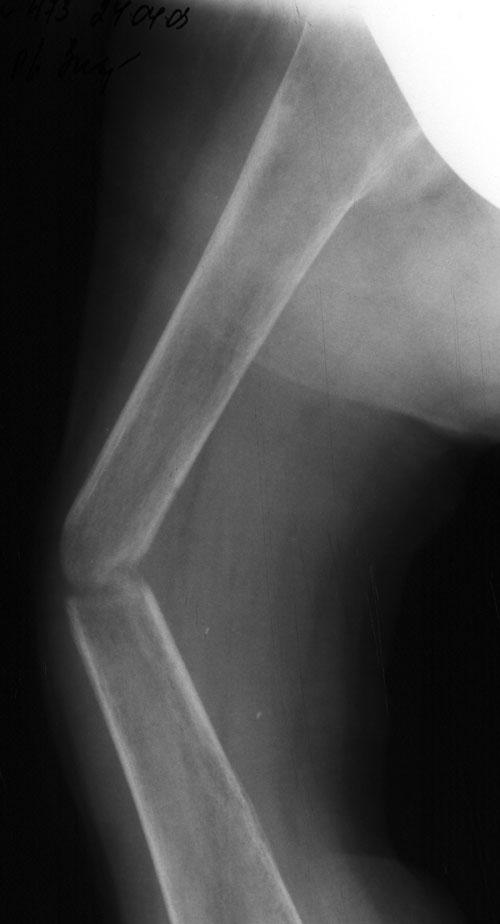

Выписка из амбулаторной карты пациента, 1980 г.р. Находится под наблюдением в поликлинике КНЦ РАН. Состоит на "Д" учёте по заболеваниям: Ювенильный идиопатический генерализованный остеопороз. Деформация грудной клетки за счёт множественных переломов грудины, рёбер. S-образный кифосколиоз грудного отдела позвоночника. Синдром гипофосфатемии неясного генеза. ВСД по кардиальному типу. Инвалид 1-й группы с детства. Последние 4 года не может передвигаться, возникают патологические переломы. Живёт в семье, материально-бытовые условия удовлетворительные. За последние 2 года состояние значительно ухудшилось - усилилась общая слабость, участились патологические переломы, которые не срастаются. Постоянно лежит в постели. Постоянный приём препаратов кальция и диеты с повышенным содержанием кальция, фосфора и белка эффекта не дают. С 11.07.2002 по 30.07.2002 г. лечился в травматологическом отделении АЦГБ с переломом костей правого предплечья со смещением. С 24.08.2002 по 08.09.2002 г. лечился в терапевтическом отделении по поводу острого бронхита с бронхоспастическим компонентом. На сегодняшний день статус. Состояние относительно удовлетворительное. В сознании. Положение вынужденное: сидя в инвалидном кресле, сам встать на ноги и передвигаться не может, туалет только с помощью родственников. Бледный, астеничный. Выраженная деформация грудной клетки, выраженный кифоз и сколиоз грудного отдела позвоночника. Экскурсия грудной клетки ограничена. Участие в акте дыхания вспомогательных межрёберных мышц. Пальпация грудной клетки безболезненна. Деформация всех крупных и мелких суставов за счёт увеличенных эпифизов. Деформация длинных трубчатых костей, мышцы рук и ног атрофичны. Температура - 36,8, ЧД - 29 в минуту. Дыхание жёсткое, проводится во все отделы. Слева от угла лопатки и в аксиллярной области влажные мелкопузырчатые хрипы, в межлопаточной области с обеих сторон свистящие хрипы. Пульс 90 ударов в минуту, ритмичный, симмитричный, слабого наполнения и напряжения. АД 120\80 мм рт. ст. Границы относительной сердечной тупости не расширены. Тоны сердца громкие, ритм правильный. Язык влажный, блестит. Живот при пальпации мягкий, не вздут, симметричный, участвует в акте дыхания, безболезненный. Печень по краю рёберной дуги. Стул регулярный, оформлен, без патологических примесей. Мочеиспускание свободное, безболезненное. Симптом Пастернацкого отрицателен с обеих сторон. Отёков нет. Анализ крови общий 26.08.2002: Hb-146 г\л, Эр.-4,8, ЦП-0,91, Лейк.-6,4, п.-4, с.-45, э.-5, м.-11, СОЭ-4 мм\ч. Анализ мочи общий 26.08.2002: Уд. вес-1025, белок-0,01, сахар-нет, лейк.-0-1 в поле зр., слизь+++, бактерии+. Анализ крови биохимический 26.08.2002: глюкоза-4,9, АЛТ-0,3, АСТ-0,5, биллирубин-11,9, креатинин-44,2, мочевина-3,8, СРБ (+). Анализ крови на микрореакцию - отрицательный. Флюрограмма за 2002: Резко выраженная деформация грудной клетки за счёт множественных переломов рёбер, грудины. Инфильтративных теней в лёгких не определяется. По сравнению с предыдущим исследованием от 01.12.2000 г. - ухудшение: нарастают деформация грудной клетки и позвоночника. ЭКГ за 2002 год: Синусовая тахикардия с ЧСС 88 в минуту. Отклонение ЭОС вправо. Признаки нарушения процессов реполяризации миокарда задней стенки левого желудочка. Повидимому, изменения ЭКГ обусловлены позиционными изменениями, возможно астеничным телосложением. Дополнительные методы исследования. Рентген правого предплечья (17.10.2002): Металлоостеосинтез по поводу перелома обеих костей правого предплечья в н\з: признаки репарации практически не определяются, сохраняется диастаз между отломками. Рентген правого предплечья (24.04.2003): Металлоостеосинтез по поводу перелома обеих костей правого предплечья в н\з: признаки репарации отсутствуют, формируются ложные суставы. Резко выраженный остеопороз. Рентген правого бедра (18.02.2003): Несросшийся перелом правого бедра на границе с\з и н\з со смещением отломков под углом открытым кнутри. Формирующийся ложный сустав. Выраженный остеопороз костей. Рентген правого бедра (24.04.2003): Угловое смещение отломков правого бедра увеличилось. Признаки репарации крайне вялые: по наружному краю отломков формируются замыкательные пластинки - ложный сустав. Выраженный остеопороз.